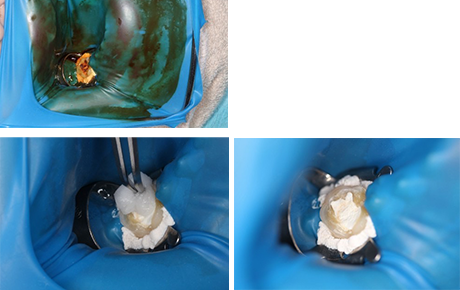

当院では、根の治療(根管治療)には、原則的にラバーダムを使用するようにしています。

口腔内の唾液の中には、おびただしい数の細菌が含まれています。そのため治療中の歯が感染しないようにラバーダムというゴムのカバーを治療する歯以外に被せることで無菌による治療を行います。

それだけでなく、ラバーダムと歯との隙間から唾液等の侵入がないよう、オラシールという汚特殊な樹脂で隙間を封鎖し、治療する歯のための環境を作ります。

このラバーダムを使用することで治療の成功率は飛躍的にあがります。